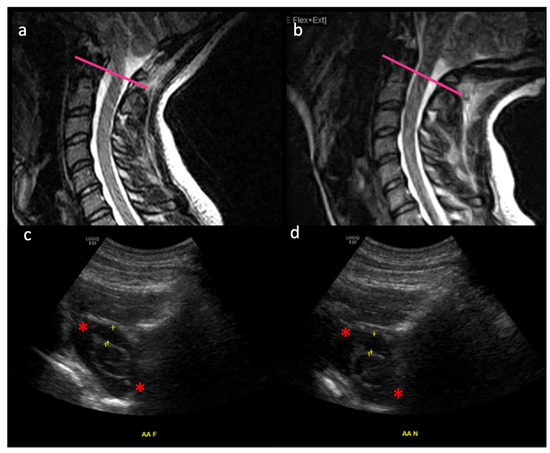

In Figure 3, MRI (a,b) and ultrasound (c,d) are shown of a healthy (non-CM1) control subject, illustrating the craniocervical junction in flexion (a,c) and extension (b,d). Intradural suspension of the spinal cord is at play helping it maintain its dorsoventral position. The subarachnoid space is dynamic between these two movements, as evidenced by the changing distance between the yellow “+” markers in Figure 3c (0.48 cm) and Figure 3d (0.55 cm). The C1 nerve roots (red asterisks) are also shown, as additional suspension structures which restrict the movement of the thecal sac and spinal cord in space at the craniocervical junction.

MRI (a,b) and ultrasound (c,d) of a healthy (non-CM1 patient) are shown, illustrating the craniocervical junction in flexion (a,c) and extension (b,d). Approximate axial level of ultrasound images is denoted by the pink line on MRI images. Intradural suspension of the spinal cord is at play helping it maintain its dorsoventral position. The subarachnoid space varies between these two movements, as evidenced by the distance between the yellow “+” markers in 2c (0.48 cm) and 2d (0.55 cm). The C1 nerve roots (red asterisks) are also shown, as additional suspension structures which restrict the movement of the thecal sac and spinal cord in space at the craniocervical junction. These are studies from a healthy volunteer. This study [1,5] was conducted in 2021 under the RIH IRB 1338182 and supported by a seed Grant sponsored by the Rhode Island Medical Imaging Department.